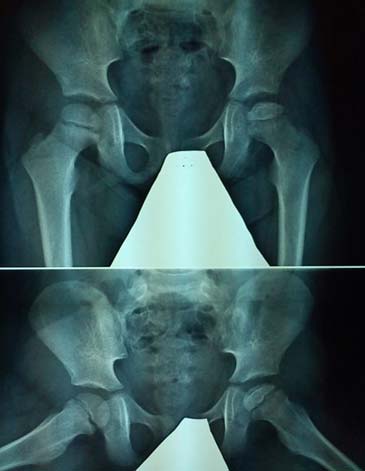

Οστεοχονδρίτιδα μηριαίας κεφαλής - Νόσος Parthes

Εικόνα Οστεοχονδρίτιδα της αριστεράς μηριαίας επίφυσης, με στοιχεία κεφαλής σε κίνδυνο. Αντιμετώπιση με οστεοτομία ραιβότητος και βελτίωση του σχήματος της μηριαίας κεφαλής.